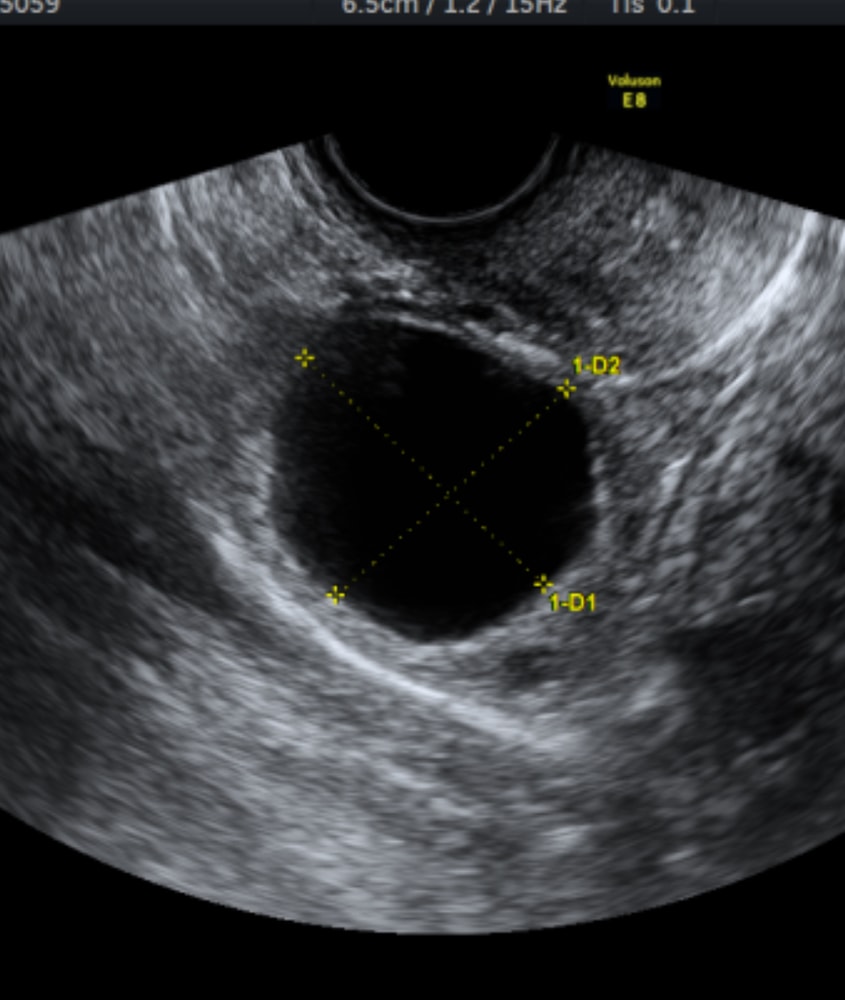

Ангелина, у меня вот такая была ,34×29 в 5 недель беременности. Потом была уже меньше и больше ее на узи не описывали. Изображениет